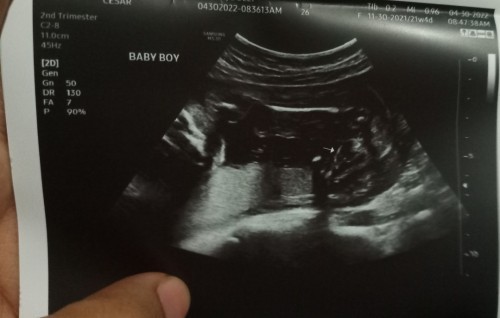

Third Baby (Boy)

Hi mommies. Pang 3rd baby ko na to 22weeks, sabi kasi ng nag ultrasound sakin 80% baby boy , nakadapa kasi si baby nun kaya di kita talaga π₯ and suhi siya. Sure na kaya bebe boy ? Praying na boy sana para sa mr ko at kota na sana. Thanks #BabyBoy22weeks